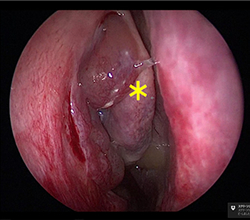

ヒトの鼻はいくつもの空洞に分かれており、それらを副鼻腔といいます(図4)。それぞれの副鼻腔は自然口という小さな通路でつながっていますが、この通路が炎症などでふさがると副鼻腔内で炎症を起こし、粘膜が腫れて粘液がたまります。この状態が長引いたものが慢性副鼻腔炎で、膿がたまると蓄膿症という状態になります。たまった粘液がさらに粘膜の炎症を引き起こし、鼻茸(ポリープ)を増生させることがあります(図5)。ポリープによってにおいの分子が嗅神経に届かないと、嗅覚障害をもたらすことがあります。嗅覚が低下すると味も感じにくくなる味覚障害を自覚することもあります。慢性副鼻腔炎を治すことで、嗅覚障害が改善します。

内視鏡で観察しています。

鼻茸(ポリープ)が確認されています。(黄色*)